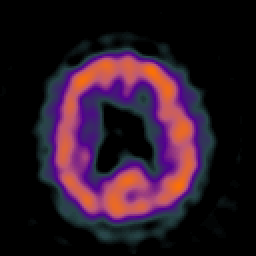

Huntington's Chorea, MR -- Slice #13

Click on sagittal image to select slice. Click on thin tickmark to change timepoint, or thick tickmark for overlay.